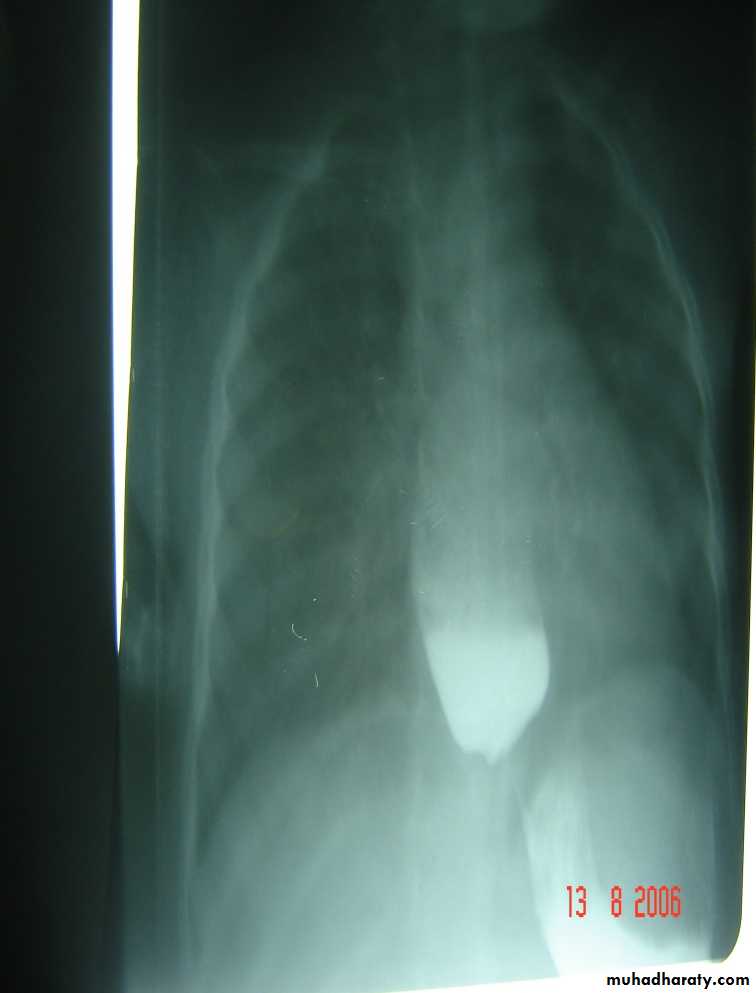

Diagnosis: achalasia cardia

Presentation:• Hailtosis

• Vomiting (not projectile)

• Wheezing

• Chest infection

Ba-swallow dilatation of esophagus with narrowing of lower part.

Treatment cardiomyotomy